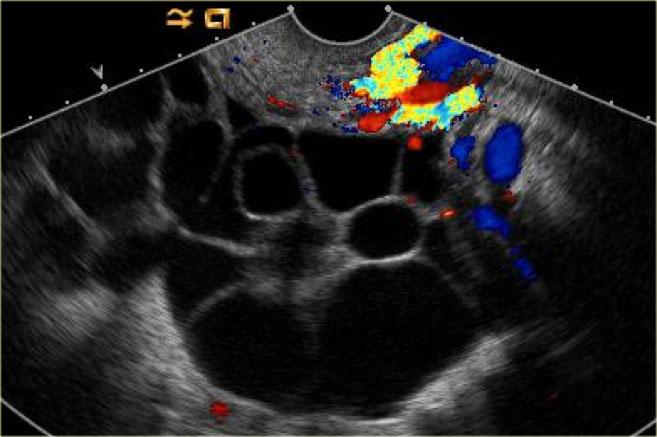

Các hình ảnh siêu âm qua ngã âm đạo cho thấy một nang buồng trứng phức tạp nhỏ với mạch máu thành nang trên phân tích Doppler năng lượng.

Hình ảnh Doppler vòng tròn đặc trưng này được gọi là dấu hiệu ‘vòng lửa’ (ring of fire).

Lưu ý, có hiện tượng xuyên âm tốt và không có mạch máu bên trong, phù hợp với nang hoàng thể đang thoái triển một phần.

Một trường hợp khác với hình ảnh điển hình của dấu hiệu ‘vòng lửa’ trên siêu âm.